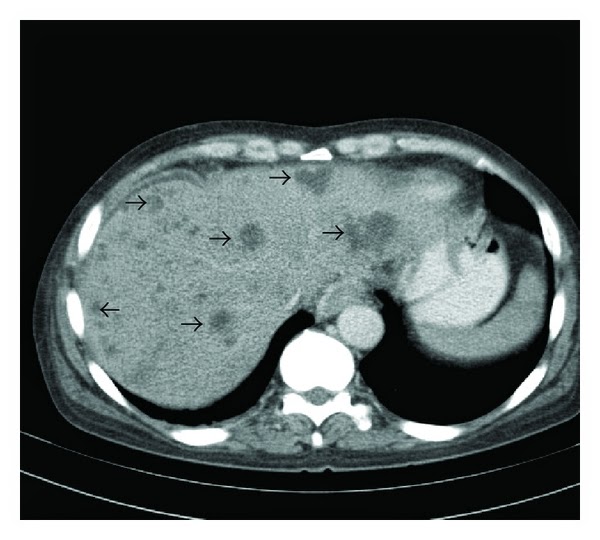

Пілефлебіт як грізне ускладнення апендициту супроводжується смертністю у 90-98% випадків. При цьому запально-деструктивний процес із гангренозно зміненого паростка переходить на його брижу і, природно, в судини системи ворітної вени, поступово поширюючись на брижові вени ілеоцекального кута, а потім по системі верхньої брижової вени - в ворітну і печінкові вени. Це найбільш грізне ускладнення гострого апендициту та інших захворювань черевної порожнини, оскільки випадки виліковування цієї патології надзвичайно рідкі. Згідно з даними деяких авторів, це можливо лише тоді, коли рано перев'язати здухвинно-ободові вени або виконати резекцію ілеоцекального кута в межах здорових тканин. Швидко поширюючись на брижові вени ілеоцекального кута, запальний процес через 2-3 дні досягає ворітної і печінкових вен. Крім того, він у ретроградному напрямку може поширюватись на селезінкову та інші брижові вени.

Зразу після апендектомії без світлого проміжку у хворих підвищується температура тіла і наростають явища важкої гнійної інтоксикації. Об'єктивно визначається метеоризм, рівномірна болючість прався половини живота без ознак подразнення очеревини. З прогресуванням процесу стан хворого різко погіршується, він втрачає у вазі, з'являється жовтяниця, збільшується в розмірах печінка, температура тіла набуває гектичного характеру, тобто наявний септичний стан. Болі переміщуються в верхню частину черевної порожнини, на фоні вираженої інтоксикації з'являються ознаки печінково-ниркової недостатності. При масивній протизапальній терапії пілефлебіт має затяжний стан, ознаки набувають стертого характеру на фоні попередньої динаміки протікання захворювання.

В міру поширення процесу на печінкові вени з 'являються клінічні ознаки синдрому Кіарі - поряд із збільшеною печінкою, жовтяницею збільшується в розмірах селезінка і виникає асцит Хворі помирають від множинних абсцесів печінки. У них спостерігається значне підвищення загальної згортальної і зниження антизгортальної активності крові - вкорочується час згортання, підвищується толерантність плазми до гепарину, знижується рекальцифікація плазми, вміст гепарину і гальмування фібринолізу. Ці зміни наростають, починаючи з 3-4-го дня після операції. В цей час можливі й такі ускладнення, як емболія гілок легеневої артерії з інфаркт-пневмоніями, а іноді й абсцедування легеневої паренхіми. З метою попередження таких ускладнень і лікування пілефлебіту хворим поряд з інтенсивною протизапальною терапією призначають великі дози гепарину під контролем коагулотрами, тромбоеластограми і відповідно, процесу зсідання крові Рівень протромбіну в крові хворих слід утримувати в межах 30-50% протягом 15-20-и діб.